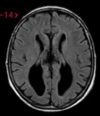

CADASIL As imagens do FLAIR mostram achados clássicos em CADASIL - hiperintensidades da substância branca confluentes com infartos lacunares e envolvimento dos lobos temporais anteriores